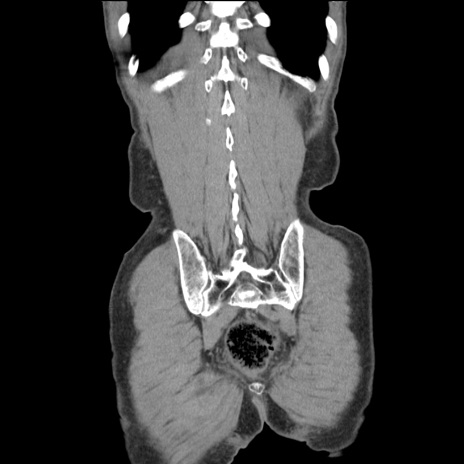

症例11(冠状断像)

【症例】 60歳代男性

【主訴】 下腹部痛

【現病歴】 本日夜中より下腹部痛の症状認め、受診。

【既往歴】 膀胱癌(膀胱全摘+尿管皮膚瘻術) 、胃癌術後

【身体所見】 BT 35.3℃、PR 58/min、BP 136/98mHg、腹部平坦、軟、腸蠕動音±、ストマ留置あり、左上腹部~正中部に圧痛あり、反跳痛なし。

【データ】WBC 5100、CRP0.01